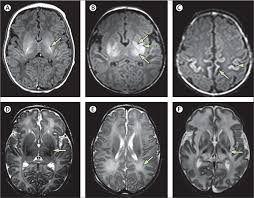

Fig. No.- 1  Brain injury (Hypoxia ischemia)

Abnormal respiratory patterns. Investigations,  Neuroimaging: Cranial ultrasound  Useful for detecting intraventricular hemmorrhage or gross structural abnormailities. )Magnetic resonance imaging (MRI): Preffered for assessing the extent of brain injury, Diffusion-weighted imaging helps identify areas of acute hypoxic-ischemic injury, Computed tomography (CT): Limited use due to radiation exposure but may be used for hemorrhagic lesions. Electroencelography (EEG): Monitors brain activity and detect seizures or abnormal patterns, Amplitude-integrated EEG (aEEG) can provide continuous monitoring in NICUs. Echocardiography: Assesses cardiac function, which may be impaired in severe hypoxic-ischemic cases.